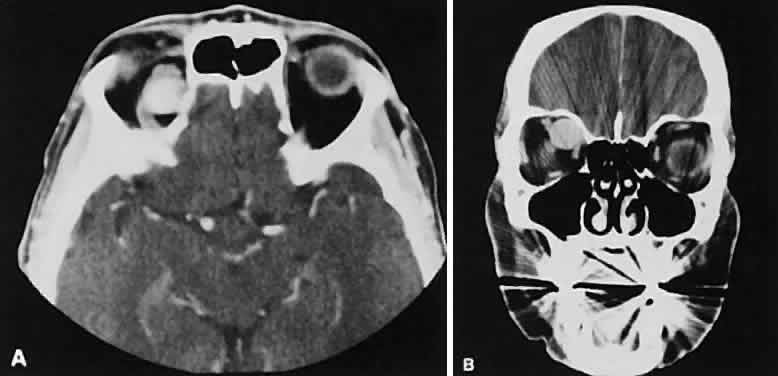

Lacrimal fossa lesions deserve separate consideration and do not fit any other convenient classification scheme. The lacrimal gland is a substrate for various tumors both benign and malignant. Benign lesions are typified by the pleomorphic adenoma (benign mixed tumor). The clinical profile of painless progressive proptosis is matched with a CT picture that shows an enlarged, sometimes nodular, well-delineated lacrimal gland (Fig. 16). Bone windows may show pressure expansion and thinning of the bone in the lacrimal fossa. Intralesional calcium61 or intralesional hemorrhage62 also may be present.

Fig. 16. Benign mixed tumor of the lacrimal gland. Axial (A) and coronal (B) views show a well-demarcated hyperdense mass that expands the fossa of the lacrimal gland by pressure effects rather than erosion. Suggestion of mixed density is apparent on the axial view, and globe displacement is evident on the coronal view.

Malignant lesions of the lacrimal gland, conversely, often appear invasive, with bone destruction evident on the CT scan (Fig. 17). Intralesional calcium may be present.63,64 The use of contrast material facilitates detection of lesions that extend beyond the confines of the orbit.

Fig. 17. Adenocarcinoma of the lacrimal gland. A. Unenhanced axial view shows the speckled calcification of a lacrimal gland tumor. B. Contrast-enhanced view at about the same level shows intense enhancement and vascularity. In axial views at a higher level, an unenhanced scan (C) is unremarkable, although a contrast-enhanced view (D) at the same level highlights intracranial extension (arrows). E. Reconstructed coronal view has bone destruction with extension into the intracranial and temporalis fossae.